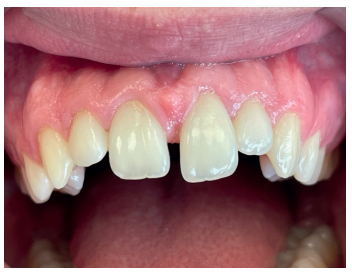

La inspección intrabucal permitió observar una disminución de la apertura bucal, junto a una herida incisocontusa a nivel de la cara interna del labio inferior, la cual fue suturada en urgencias. Al observar la oclusión se vio que el paciente presentaba ligera luxación palatina de los dientes anterosuperiores, los cuales, dada la situación de mordida abierta del paciente, no imposibilitaban la oclusión (Figura 3). Dicho grupo dental presentaba ligera movilidad y dolor a la percusión vertical y horizontal, presentándose todos ellos con vitalidad positiva. Los tejidos blandos se observaron con características de normalidad.